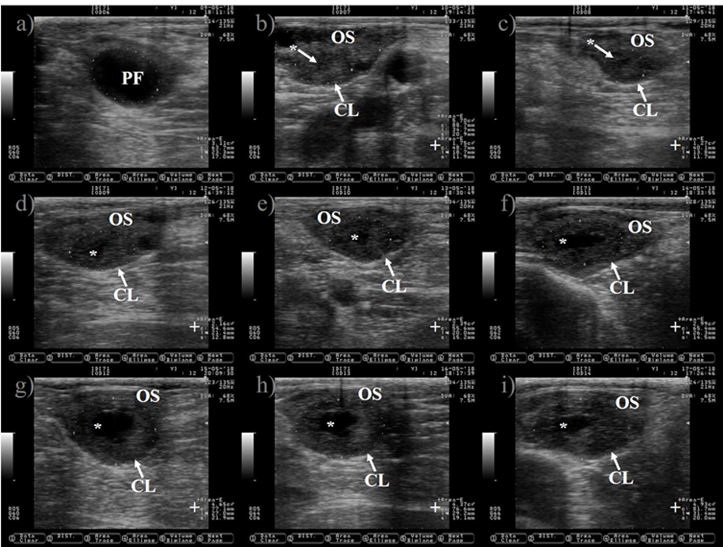

Pictures were taken at approximately every 24 h from day before to 7 d after ovulation. a) preovulatory follicle (PF). b) early CL after ovulation of the PF, notice the presences of luteal cavity (*), the CL and the ovary stroma (OS) are almost isoechogenic until 2 d after ovulation (b-d), but the CL becomes darker (hypoechogenic) than the OS as it ages (c-i). e) the CL is well differentiated from the OS at 3 d after ovulation. f-i) pictures depict a growing CL, the luteal cavity is clearly identified at this stage (4-7 d after ovulation). i) the CL has almost triple its area (+) since ovulation day (b). Pictures were taken using a 7.5 MHz probe.

Figure 4 Growth of the corpus luteum (CL) after ovulation in Holstein dairy cattle

Ovulation is expected to occur after estrus. However, 3.4 and 12.4 % of cows did not ovulate after estrus during the cool and warm season in a study carried out in Spain22. Ovulation failure (anovulation) completely blocks the opportunity of pregnancy. Therefore, disappearance of the preovulatory follicle (ovulation) should be confirmed by ultrasound after estrus (Figure 4).

The CL is a transient endocrine ovary gland that regulates the length of the estrous cycle and produces progesterone to create a suitable uterine environment for pregnancy. The CL originates from the transformation of granulosa and theca follicular cells into large and small luteal cells triggered by the preovulatory LH peak30. The tracking of the growth of the CL during the estrous cycle might begin at 12 to 24 h after ovulation (Figure 4)31. The CL reaches its maximum size between days nine and 10 of the estrous cycle32,33. It appears as a semi-circle solid shape structure or with a central cavity (Figure 5). The cavity is filled with a serous transudate or blood34. The incidence of CL with cavities might reach up to 79%31. The ovulation of larger follicle predisposes to cavities formation35, without compromising progesterone production or pregnancy rate in Holstein cattle35,36.

The measurement of the CL after insemination is relevant because blood progesterone concentration at mid-luteal phase depends on its size37 and a positive association between progesterone concentrations and area of the growing CL has been reported38. In addition, dairy cattle with good genetic merit for fertility traits have greater blood progesterone concentrations and bigger CL than those with poor genetic merit39,40. The CL grows faster in pregnant than in non-pregnant cows from day six to nine of the estrous cycle41, a reason to explain the difference in CL growth rate is unknown. However, a faster growth rate might be associated with a healthier corpus luteum.

The analysis of CL ultrasound images has been performed to predict the stage of the estrous cycle and its functional status (growing or regressing). During the diestrus, the CL is darker, and its echotexture is more homogenous than during the metestrus and proestrus34. However, the functional assessment of the CL is difficult to determine by ultrasound images33,42. Corpora lutea at diestrus stage are easily identified, but to differentiate between those in metestrus (growing CL) and proestrus (regressing CL) is hard because of its morphological similitudes (Figures 4 and 7). In addition, when the area of the CL is between 1.3 and 3.2 cm2, it also difficult to determine if functional CL exists43. Therefore, to establish the functional status of the CL, it is necessary to perform multiple progesterone concentration analysis, to review the animal reproductive record or to carry on more than one CL measurement by ultrasound at least 2 d apart. In addition, the assessment of luteal blood flow by doppler ultrasound can be used to stablish corpus luteum functionality44.

The CL undergoes regression if pregnancy is not established. Regression of the CL is under the uterine prostaglandin (F2α) command. A loss of progesterone synthesis capacity and reduction in the size of the CL is observed during the stage of regression (Figure 6). The CL begins to shrink after d 14 of the estrous cycle33 or 3.2 d before the onset of estrus in non-pregnant cows32, but becomes sensitive to the luteolytic effects of prostaglandins at d 5 of the estrous cycle45. Prostaglandin reduces the size of the CL (23 to 47 %) within one to four days46 and decreases blood concentration of progesterone within 4 h post-injection by ceasing steroidogenic enzymes activity47 and by inducing luteal cell death48. In addition, the CL is colonized by immune cells49 that remove dead cells from the ovarian stroma during regression48, contributing to CL reduction in size at this stage. After regression of the CL, a preovulatory follicle and estrus will appear, remaining only trace of the former CL on the ovary (Figure 7). However, if pregnancy is established, uterine prostaglandin (F2α) synthesis is blocked. Therefore, regression does not occur and the CL extends its life span until the end of the next reproductive event (pregnancy).